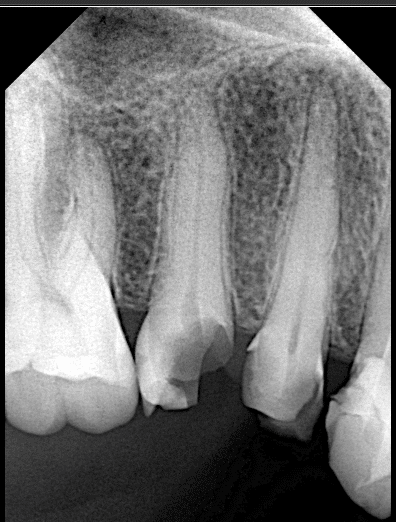

Initial situation showing large carious lesion in the upper premolars

Pre-operative x ray